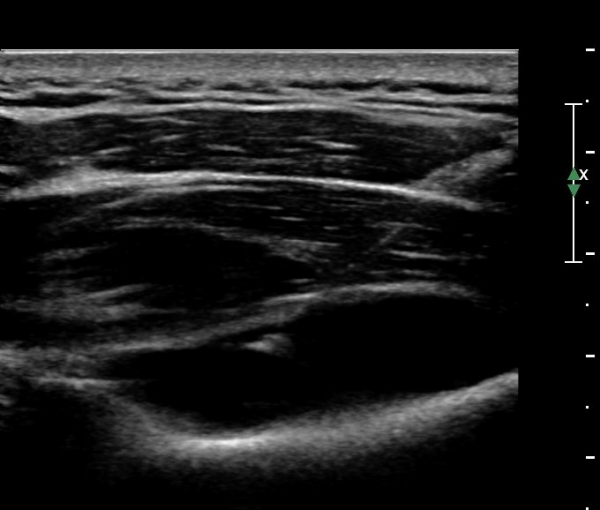

¾î±ú µÚÂÊ È¾´Ü¸é°Ë»ç¿¡¼­ °üÀý¿Í(glenoid) ³»Ãø¿¡¼­ ¸¹Àº ¾çÀÇ ¼ö¾×Àú·ù°¡ °üÂûµÈ´Ù(»çÁø 1, 2).